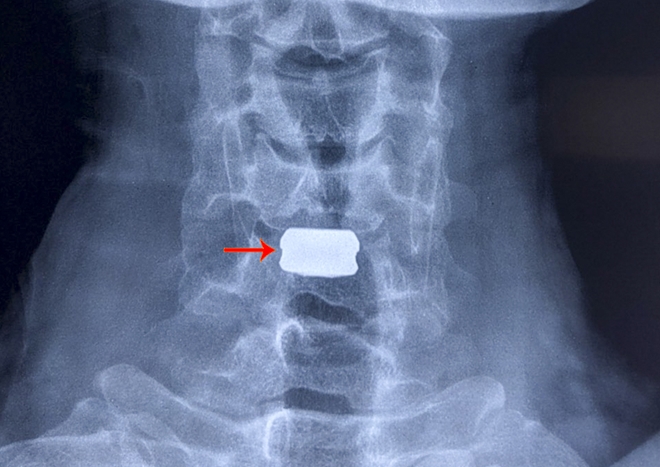

Theo đó, bệnh nhân Bùi Văn Sang (SN 1975, ngụ TP Cần Thơ) có triệu chứng đau cột sống cổ, tê và yếu tay chân đã nhiều tháng, không đi lại được nên đến BVĐKTƯCT thăm khám. Tại đây, qua hình ảnh X-quang; cắt lớp điện toán và cộng hưởng từ cột sống cổ, bệnh nhân được chẩn đoán mắc bệnh lý tuỷ cổ do thoát vị đĩa đệm tầng C5-6 chèn ép tuỷ sống cạnh trung tâm lệch phải. Bệnh nhân được chỉ định thay đĩa đệm nhân tạo đốt sống cổ ở tầng C5-6.

Ê kíp BSCK2 Huỳnh Thống Em; Ths-BS Nguyễn Hữu Thuyết; BSCK1 Lưu Tuyết Kiều tiến hành phẫu thuật cho bệnh nhân. Các BS tiến hành cắt đĩa, lấy nhân nhầy giải áp cho tủy và rễ thần kinh tại chỗ. Thời gian phẫu thuật hơn 1 giờ. Sau phẫu thuật, ngày thứ 3 bệnh nhân có thể tự nằm nghiêng, tự đi lại được mà không cần hỗ trợ.

| Và sau khi phẫu thuật thành công. |

Theo BSCK2 Huỳnh Thống Em, Giám đốc Trung tâm chấn thương chỉnh hình BVĐKTƯCT, để điều trị bệnh lý tủy – rễ cổ nguyên nhân do khối thoát vị chèn ép vào tủy sống thường được lựa chọn phẫu thuật với phương pháp cắt đĩa đệm, lấy khối nhân nhầy để giải áp, sau đó 2 tầng đốt sống được hàn cứng lại bằng nêm PEEK cộng với nẹp vít.